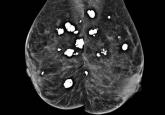

ArticleBreast calcifications mimicking pulmonary nodulesAuthor:Moiz Salahuddin, MDPublish date: August 1, 2017Radiography suggested the lesions were in the lungs, but CT and mammography said otherwise.Read More